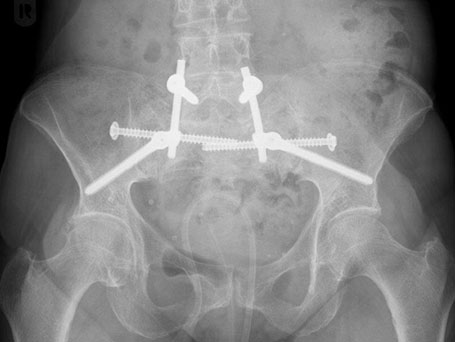

Patientin mit beiderseitigem Bruch des Kreuzbeins und Querfraktur (U-Shaped fracture). Stabilisation über beiderseitige Verschraubung auf S1-Höhe sowie spinopelvine Stabilisation über Schrauben – Stabsystem führt zu einer Stabilisation des hinteren Beckenrings, sodass der Knochen im weiteren Verlauf trotz der Belastung heilen kann.

OPERATIVE VERSORGUNG DER PATIENTIN

Beiderseitige Verschraubung auf S1-Höhe sowie spinopelvine Stabilisation über Schrauben-Stabsystem

89-jährige Patientin mit Beckenringfraktur beidseits transsacral und rechtsseitigem vorderen Schambein und Sitzbeinbruch. Auch im Nachhinein konnte anhand der zuerst auswärtig erstellten Röntgenbilder kein Bruch erkannt werden. Bei der ersten Vorstellung hier 4 Wochen nach dem Unfall zeigten die Kontrollbilder dann eindeutig die Verletzung und wir veranlassten eine CT Untersuchung. Bei den Beckenbrüchen der alten Patient*innen kann in vielen Fällen ohne Operation behandelt werden. Bei anhaltenden Schmerzen sollte jedoch erneut Diagnostik erfolgen und dann gegebenenfalls auch eine operative Stabilisation durchgeführt werden, um eine chronische Fraktur und die damit verbundenen Schmerzen und Immobilität zu vermeiden.

Es wurde bei der Patientin eine Verschraubung des Beckens durchgeführt und damit die Situation so stabilisiert, dass die Patientin wieder mobilisiert werden konnte.